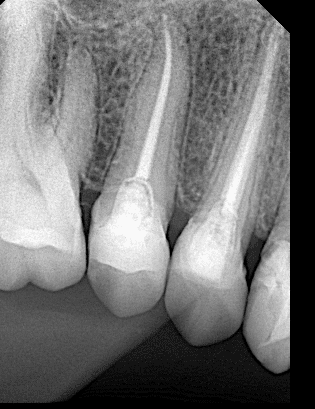

After obturation

After preparation

Final x ray